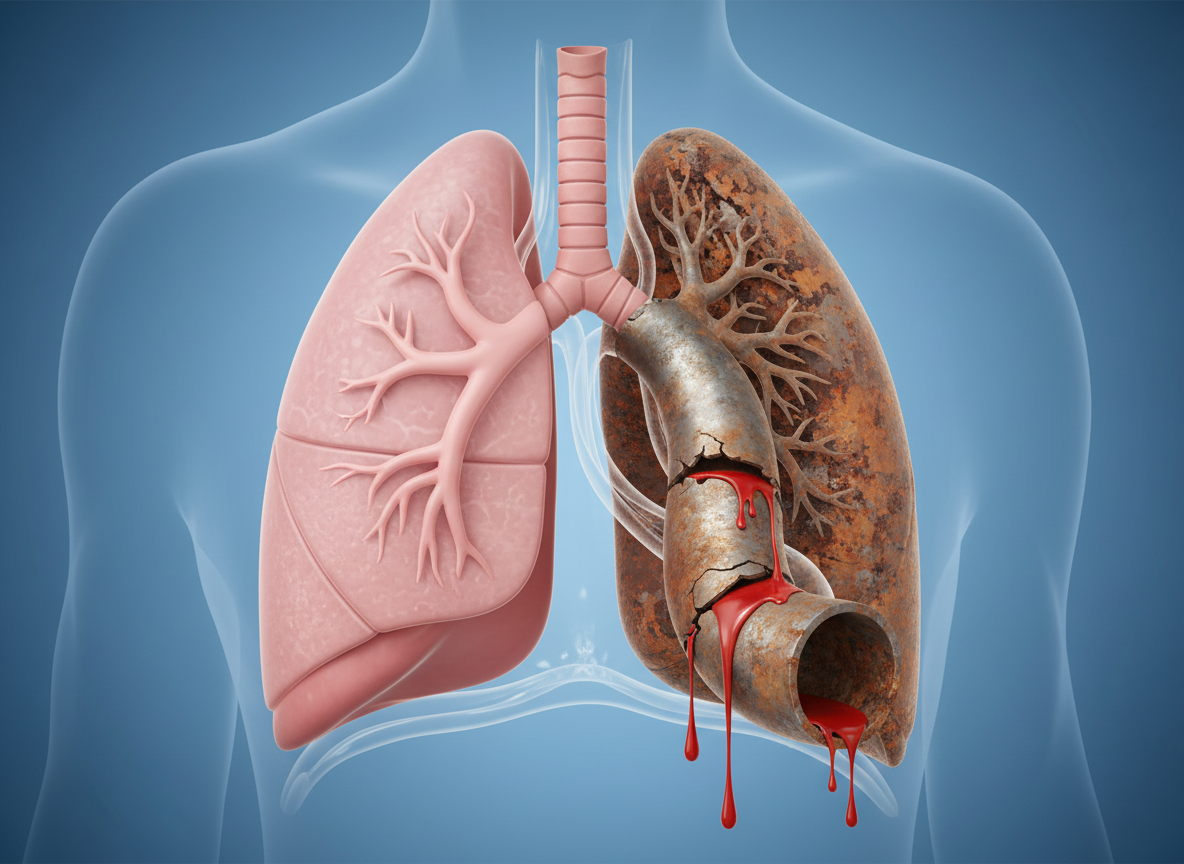

객혈의 가장 흔한 원인 중 하나는 '기관지확장증'입니다. 병명이 조금 어렵게 느껴지시나요? 쉽게 비유하자면, 우리 몸의 기관지를 '수도관'이라고 상상해 보세요. 오래된 수도관이 녹슬고 늘어나면 작은 충격에도 쉽게 균열이 생기고 물이 새어 나오겠죠?

기관지확장증이 바로 그렇습니다. 과거에 앓았던 결핵이나 폐렴의 흔적으로 기관지가 영구적으로 늘어나고 벽이 약해진 상태입니다. 이 경우 피로하거나 감기에만 걸려도 혈관이 터지며 피가래가 나올 수 있습니다. 많은 분들이 "저는 담배도 안 피우는데요?"라고 반문하지만, 어릴 적 앓았던 홍역이나 백일해가 원인이 되어 성인이 된 후 증상이 나타나기도 합니다. 만약 아침마다 누런 가래가 끓고 종종 피가 비친다면, 폐 CT를 통해 내 기관지 상태를 점검해 보는 것이 현명합니다.